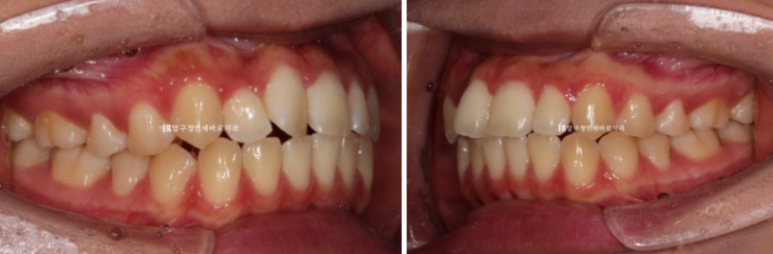

24.05

치료시작 5개월째의 모습입니다.

앞니 부분교정은 앞니 6개에만 장치를 붙여서 진행합니다.

덧니는 거의 해결이 되었고 고무줄을 걸어서 앞니 교합이 깊어지도록 도모했습니다.

심한 덧니를 가지런하게 하기 위해 치간삭제도 소량 했습니다.